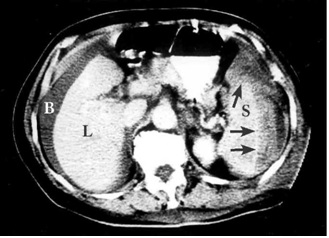

- טומוגרפיה ממוחשבת (CT) היאאמצעי חשוב ביותר לאבחון של קרעים בטחול של חולה יציב. בטומוגרפיה ממוחשבת ניתן לראות את אופי הקרע, את כמות הדם בבטן וגם ניתן לקבל מידע על נזק לאיברים אחרים (תצלומים 1-2.11). בטומוגרפיה ממוחשבת ניתן לראות גם דלף של חומר ניגוד המוזרק דרך הווריד במהלך הבדיקה אל מחוץ לטחול. דלף זה הוא סימן חשוב לדימום פעיל מהטחול ומהווה הוריה יחסית לניתוח של החולה